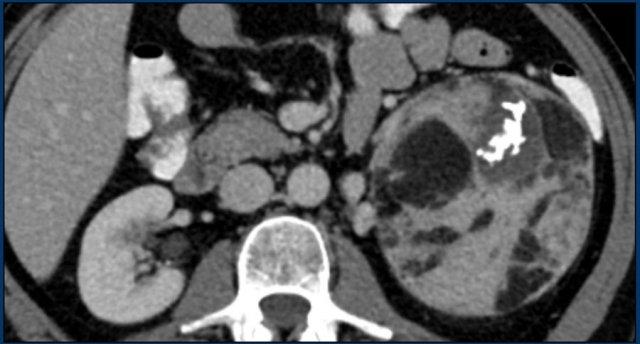

Hình ảnh cho thấy một khối không đồng nhất, bờ không rõ, kích thước lớn hơn 4 cm.

Có vùng trung tâm ngấm thuốc kém, nhiều khả năng là do hoại tử trung tâm.

Trong trường hợp cụ thể này, sinh thiết đã được thực hiện và cho thấy ung thư biểu mô tuyến, có thể xuất phát từ ung thư phổi nguyên phát.

Tuy nhiên, điều đáng ngạc nhiên là phân tích hình ảnh toàn diện, bao gồm cả FDG PET-CT, không phát hiện được khối u nguyên phát.

Hình ảnh cho thấy một tổn thương ngấm thuốc không đồng nhất, bờ tương đối rõ, kích thước 67 mm.

Sau phẫu thuật cắt bỏ, tổn thương được xác định là ung thư biểu mô vỏ thượng thận.

Hình ảnh cho thấy một tổn thương không xác định kích thước lớn với tỷ trọng không đồng nhất và vỏ vôi hóa một phần.

Sinh thiết cho thấy u cơ trơn tuyến thượng thận.

Tổn thương đã được phẫu thuật cắt bỏ.

Đây là tổn thương không xác định, ngấm thuốc không đồng nhất, bờ tương đối rõ.

Tổn thương được xác định là u tủy thượng thận (pheochromocytoma).

Tổn thương tuyến thượng thận ngấm thuốc mạnh kích thước 7 cm với các ổ nang nhỏ.

Tổn thương được phẫu thuật cắt bỏ do kích thước lớn và đặc điểm hình ảnh không xác định.

Kết quả mô bệnh học xác định đây là u tuyến (adenoma).